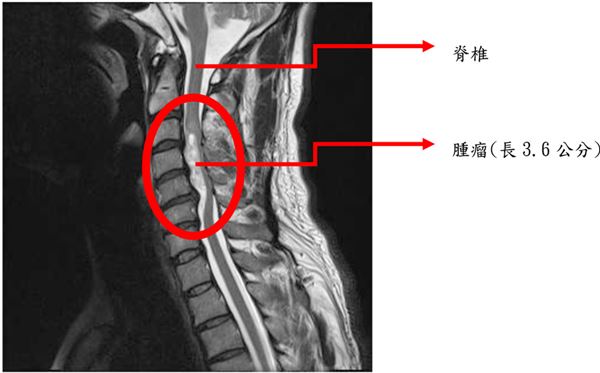

第二類是生長在於硬膜內但是在脊髓軟膜外( extramedullary )的腫瘤,多半是良性瘤,最常見的是神經鞘瘤( schwannoma )及硬膜瘤( meningioma ),一般而言可經手術安全切除而不對神經功能造成任何影響。

脊椎管腔內良性腫瘤不會轉移到其他部位,也不會有立即性生命危害,但因生長在脊椎管腔內,體積大時會壓迫脊髓神經,產生類似坐骨神經痛的症狀,嚴重時會導致下半身癱瘓。故如遇無法改善的坐骨神經痛便應及早尋求腦神經外科專科診治。

原發性脊椎內腫瘤多數都可以用精湛的顯微手術徹底切除,以絕後患。硬膜內脊髓外腫瘤多為良性瘤,手術治療有非常好的成效,脊髓內的腫瘤以室管膜瘤最為常見,一般認為摘除非常困難危險性很大,事實不然。在精細的顯微手術下配合手術中誘發電位的監測,這類腫瘤多半可以完全切除,永絕後患。